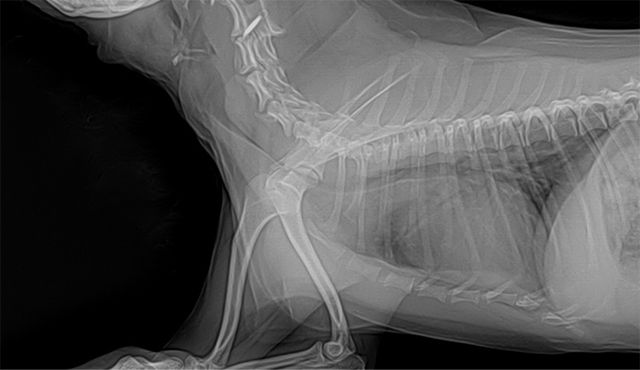

소형견을 많이 키우고 있는 한국에서는 거의 대부분이 기관지 협착으로 내원하는 편이다. 협착은 소형견종에서 선천적 이상에 의해 생길 수 있다. 이러한 선천적 소인이 지속적인 염증이나 다른 악화 요인(대부분이 비만)에 의해서 악화된다. 증상을 보이는 개는 급속도로 악화되면서 노력석 호흡이 증가되고 만성 염증과 기침을 보일 것이다(그림 7).

그림 7. 강아지에서 흡기시 심한 기관지 협착의 방사선 사진

상부기도 폐색, 감염성 기관기관지염, 심비대 혹은 심부전 또는 기생충성 질환, 담배연기, 구강 질환과 관련하여 악화될 수 있다. 노력성 호흡과 기침 시 나타나는 흉강 내 압력과 기도 압력 변화가 기도를 좁하지게 하고 등쪽 인대를 신장시키게 된다. 심한 협착시 점막의 떨림이나 신체적 손상이 기침을 더욱 자극할 것이다. 염증 또한 기침과 협착이 점점 심해지게 한다. 기관협착은 대부분 임상증상과 경부, 흉부방사선 결과를 바탕으로 진단하며, 심한 경우는 기관지경으로 정밀하게 검사를 한다(그러나 전신마취를 해야 하기 때문에 신중하게 선택 후 검사해야 할 것이다). 치료로는 내과적 처치와 체중감량이 좋은 효과를 일으킨다고 알려져 있다. 내과적 치료에 더 이상 반응을 하지 않는 동물은 스텐트 삽입술(tracheal stenting)을 고려하게 된다. 그러나 환자마다 기침시 기관 내강의 압력이 다 다르기 때문에 스텐트의 유지성에 의문을 품게 된다(모든 질환에서 외과적 수술은 항상 모든 사항을 고려해서 실시해야 된다고 생각한다).